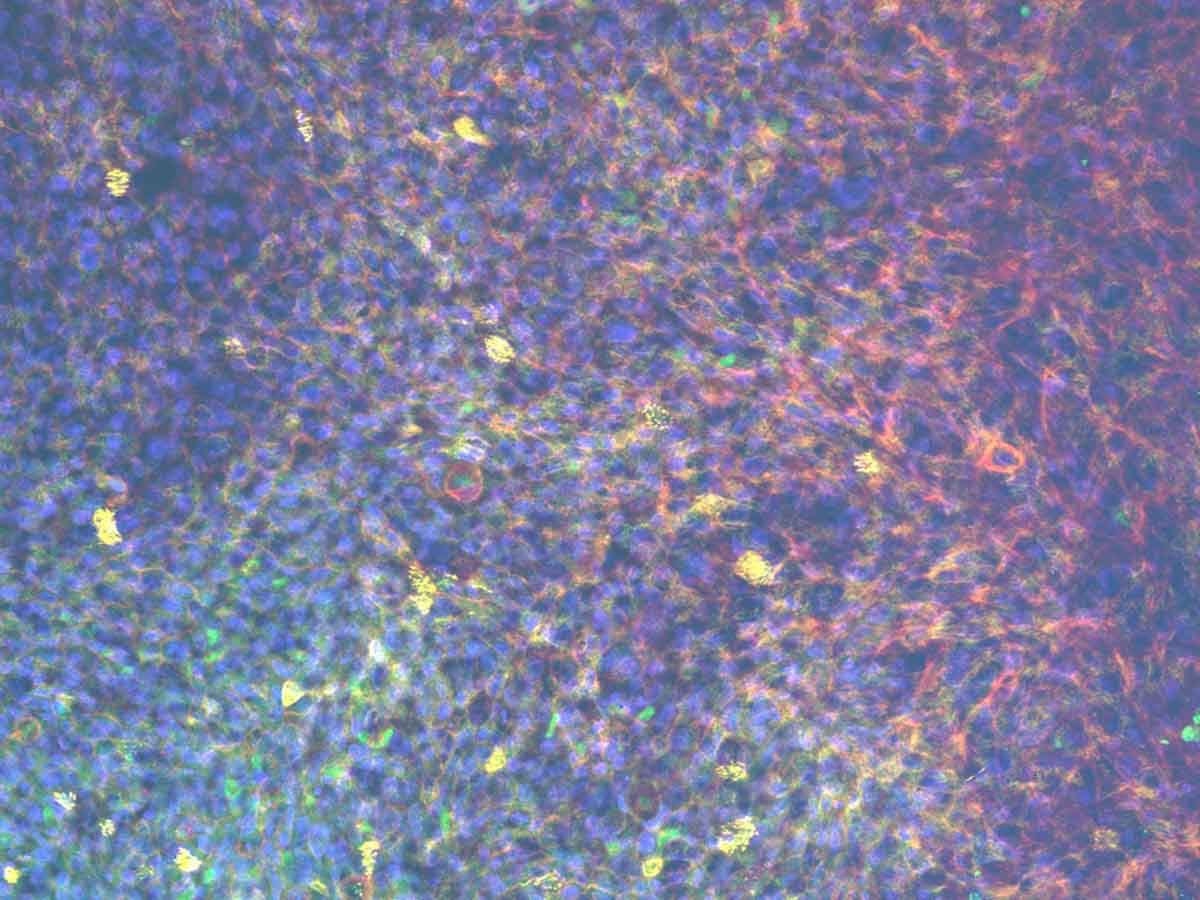

Primary human bronchial epithelial and endothelial cells are cultured on either side of an insert scaffold at air-liquid-interphase (ALI) to produce a pseudostratified epithelium over 14 days.

Culturing in perfusion enhances the differentiation of the bronchial epithelium with a functional mucociliary barrier retained for long-term culture.

We have two lung-on-a-chip – also known as Lung microphysiological systems (MPS) – an alveolar and bronchial model. The human alveolar model contains primary cells which differentiate to type I and type II pneumocytes over 14 days, with formation of alveolar sac-like formations and production of surfactant by stable type II cells. The bronchial model forms a functional pseudostratified epithelium containing ciliated, goblet, club, and basal cells. Both models can also be co-cultured with pulmonary endothelial cells to reproduce the pulmonary-vasculature interface.

Have you characterized single cell transcriptomics of the lung-on-a-chip model?.

We also focus on the cell phenotypes formed after differentiation at air-liquid interface (ALI), particularly the alveolar and bronchial epithelial cell phenotypes, to ensure they are forming lung tissues that resemble the human lung. For example, when thinking about the alveolar model we ensure that the cell population remains at a good ratio of alveolar epithelial type I (ATI) to alveolar epithelial type 2 (ATII) cells. In other model systems this balance is often skewed towards an ATI alone population which is not representative of in vivo alveoli.